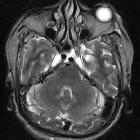

Ectopic

internal carotid artery presenting as an oropharyngeal mass. Magnetic Resolution Angiography after gadolinium administration shows the helicoids-ectopic course of the right ICA, immediately after the carotid bulb. Notice also, the significant stenosis of the controlateral left ICA.